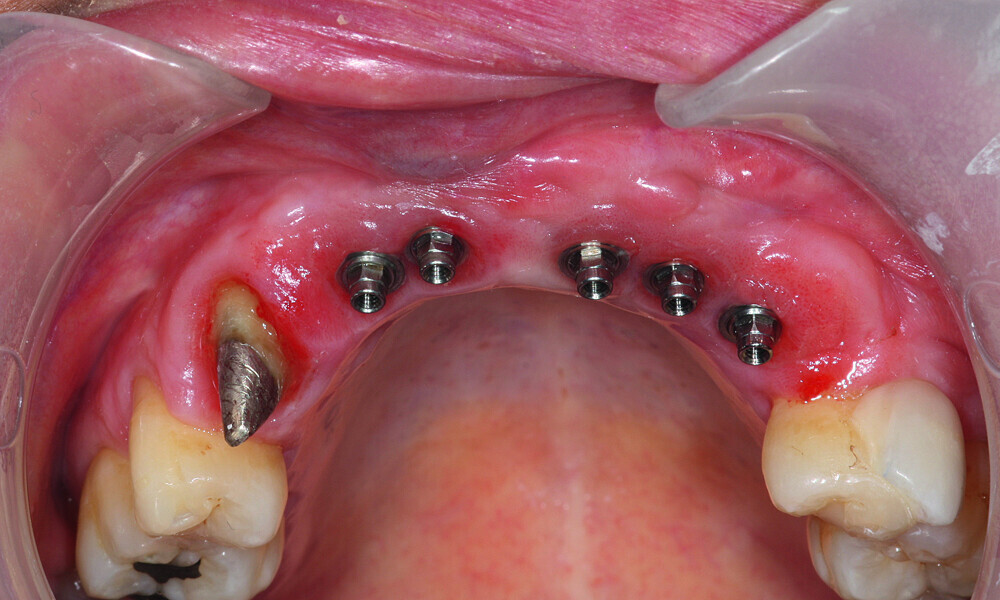

Fig. 15: Aadva self-tapping implants were placed.

Fig. 16: All five implants equipped with threaded cover screws and the surrounding tissue sutured.

Fig. 17: Loaded implants, healing abutments in situ.